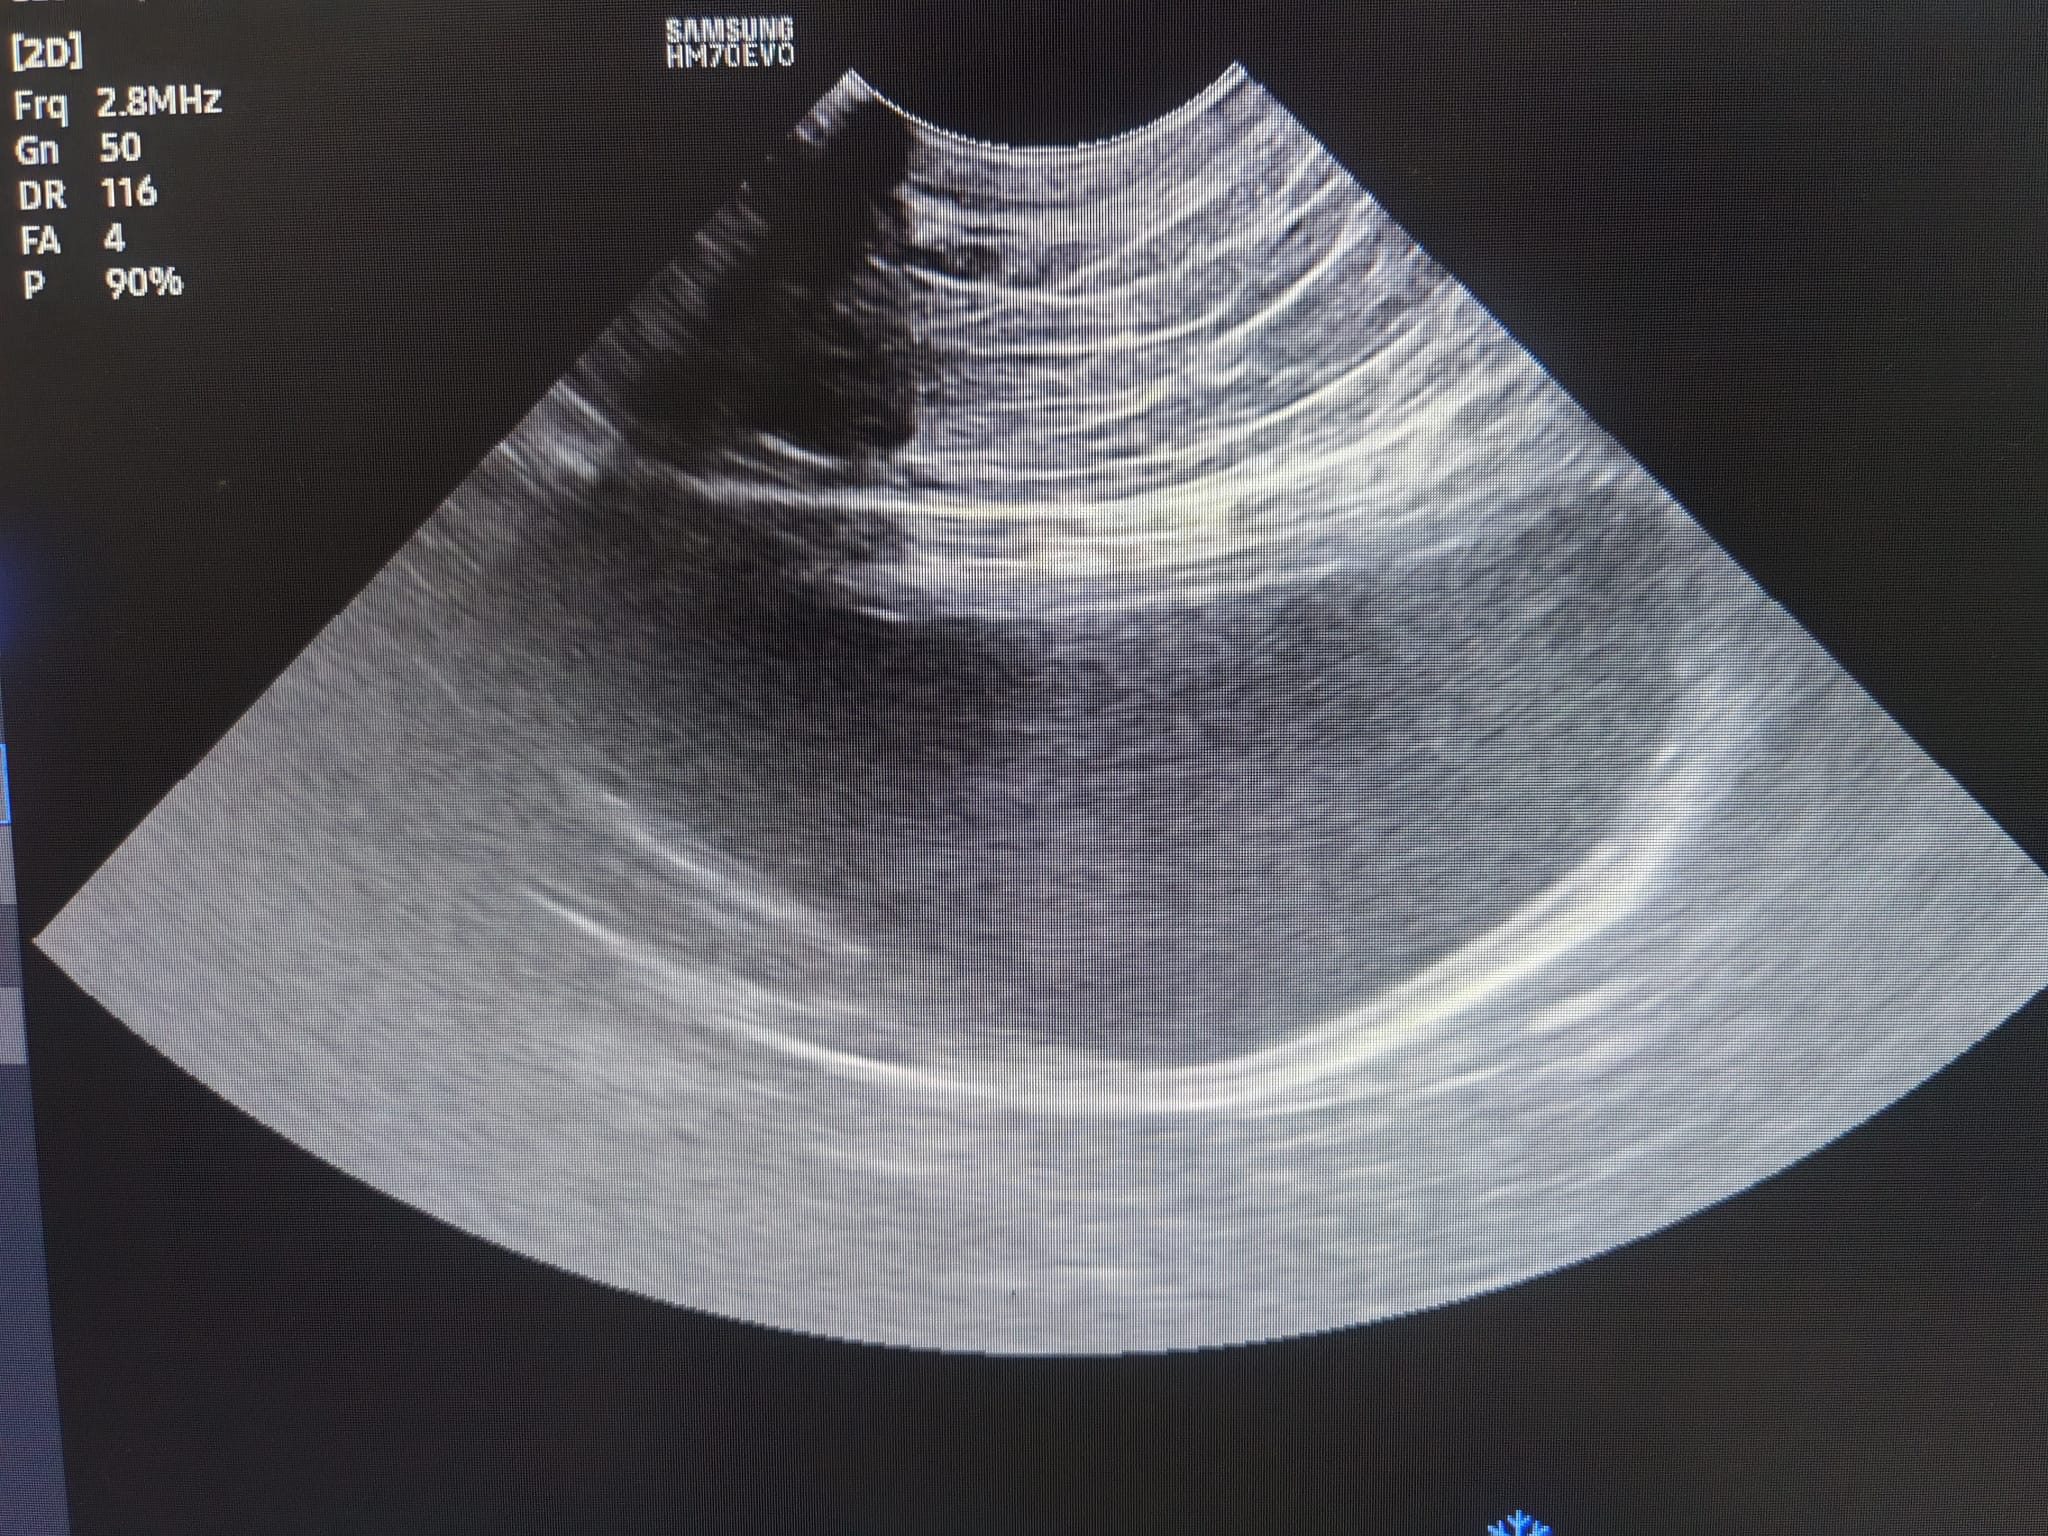

11.04am: n:”did a quick lateral abdo since we’re in that position for backleg xrays, no bladder stones seen, also did a quick bladder scan – confirm no stone inside bladder. melox is injection or oral u have? no need bupre for now unless still painful but would prefer gaba over bupre. no need antibiotics” – I’ll prep meloxicam inj n oral tmr, ill give jab and let jo/mmm help oral if I’m not in. GABA they can give tmr I’ll prep. Today he covered by methadone.

“HeiBai bladder scan – no obvious stones, anechoic lumen, mild lining irregularities.

let me know if u keen for (the specialist opinion)? alternatively we can assess his hock after medications and *if not better*, we try give him gaba before nxt vet visit to try a VD view of his hocks before i submit to specialist for interpretation”